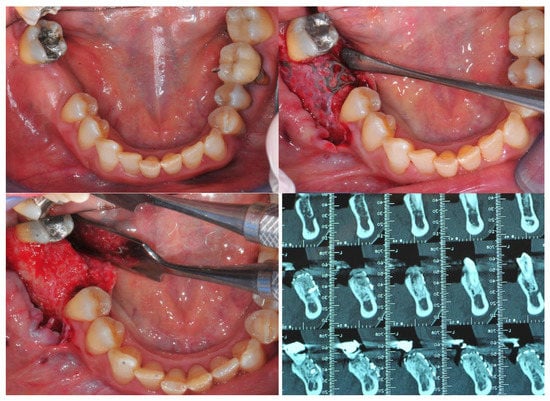

Not less than six months after CBR, a CBCT was scanned for all the patients (T1) to control the outcomes of the surgery after the graft healing phase (6–12 months) (Figure 4 and Figure 5).

Figure 4.

This composite resumes the surgical workflow from the custom Ti Mesh graft healing to the implant placement. In the CBCT (T1) screenshots it is possible to appreciate the bone volume gain. From the top left clockwise: starting situation, grid removal after 6 months; section of CBCT shows the bone volume gain, occlusal view just before implant surgery.

It was possible to compare the Dicom file derived from T0 e T1 CBCT scan exams to evaluate all these CBR procedures and the bone gain from a bi/tridimensional aspect.

First of all, through dedicated software (Real Guide Universal Open System 3 Diemme), all the Dicom format files were converted to .stl format files (known as a segmentation process).

After that, through other dedicated software (Exocad GmbH-specific tool “cross section view”), it was possible to superimpose T0 e T1 CBCT scans to trace and evaluate the linear maximum vertical and horizontal gains for all the patients (in mm) and bone volume gains for all the grafted sites (in mm3) (Figure 6 and Figure 7).